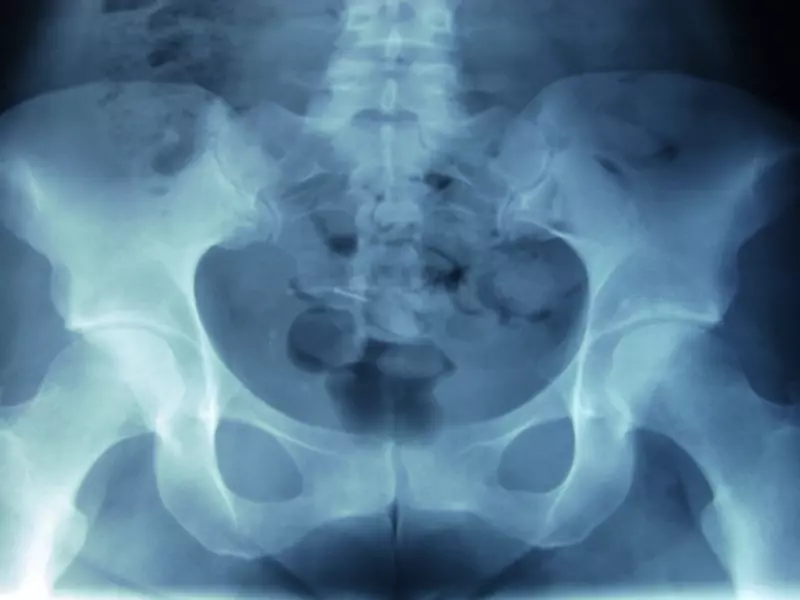

Czerwone flagi

IBS jest zbiorem niespecyficznych objawów układu pokarmowego, należy zatem zwrócić szczególną uwagę na występowanie tzw. czerwonych flag (ang. red flags), czyli niepokojących objawów dodatkowych, które mogą świadczyć o poważnej chorobie układowej (tabela 2). Przy ich stwierdzeniu należy skierować pacjenta do lekarza specjalisty celem poszerzenia diagnostyki [9].

ból biodra (ropień mięśnia biodrowo-lędźwiowego) |

ból: brzucha, miednicy, krzyża i/lub kręgosłupa |

ból kręgosłupa promieniujący do kończyn dolnych |